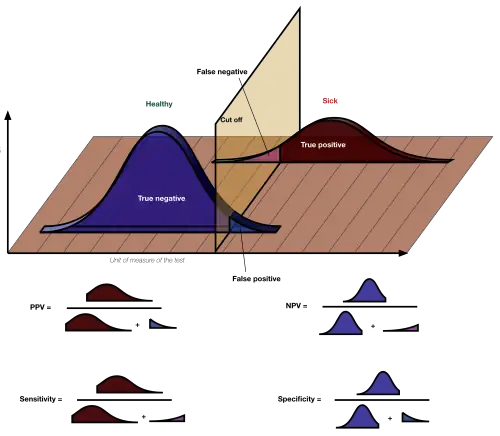

In medicine and statistics, sensitivity and specificity mathematically describe the accuracy of a test that reports the presence or absence of a medical condition. If individuals who have the condition are considered "positive" and those who do not are considered "negative", then sensitivity is a measure of how well a test can identify true positives and specificity is a measure of how well a test can identify true negatives:

- Sensitivity (true positive rate) is the probability of a positive test result, conditioned on the individual truly being positive.

- Specificity (true negative rate) is the probability of a negative test result, conditioned on the individual truly being negative.

If the true status of the condition cannot be known, sensitivity and specificity can be defined relative to a "gold standard test" which is assumed correct. For all testing, both diagnoses and screening, there is usually a trade-off between sensitivity and specificity, such that higher sensitivities will mean lower specificities and vice versa.

Sensitivity

Consider the example of a medical test for diagnosing a condition. Sensitivity (sometimes also named the detection rate in a clinical setting) refers to the test's ability to correctly detect ill patients out of those who do have the condition.[4] Mathematically, this can be expressed as:

Specificity

Consider the example of a medical test for diagnosing a disease. Specificity refers to the test's ability to correctly reject healthy patients without a condition. Mathematically, this can be written as:

Graphical illustration

-

A graphical illustration of sensitivity and specificity

A graphical illustration of sensitivity and specificity

The above graphical illustration is meant to show the relationship between sensitivity and specificity. The black, dotted line in the center of the graph is where the sensitivity and specificity are the same. As one moves to the left of the black dotted line, the sensitivity increases, reaching its maximum value of 100% at line A, and the specificity decreases. The sensitivity at line A is 100% because at that point there are zero false negatives, meaning that all the negative test results are true negatives. When moving to the right, the opposite applies, the specificity increases until it reaches the B line and becomes 100% and the sensitivity decreases. The specificity at line B is 100% because the number of false positives is zero at that line, meaning all the positive test results are true positives.